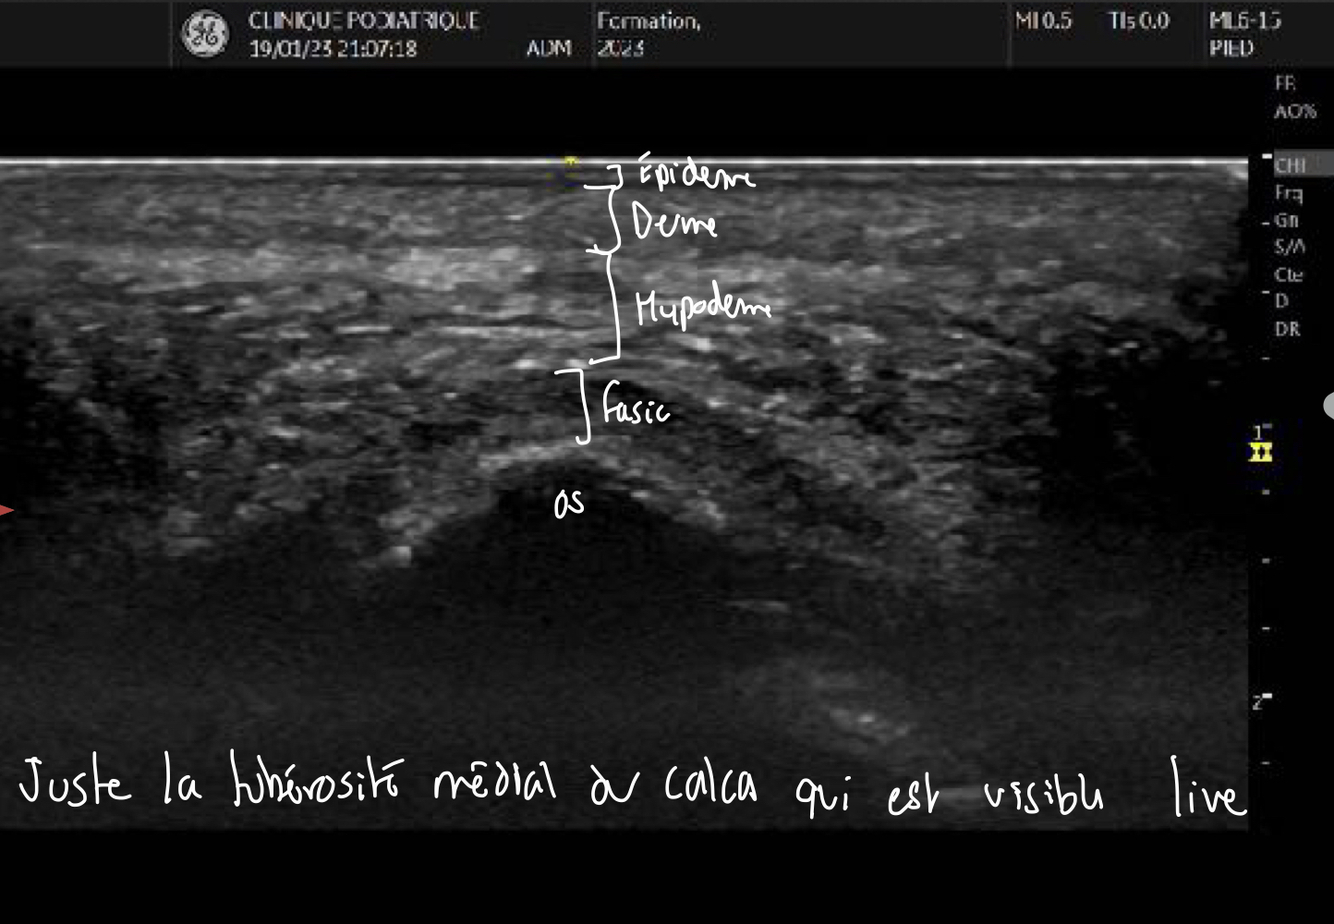

Q

Identifie la région du pied analysée ici

A

Il s’agit de la tubérosité médial du calcanéus avec le fascia et les épaisseurs de la peau au dessus